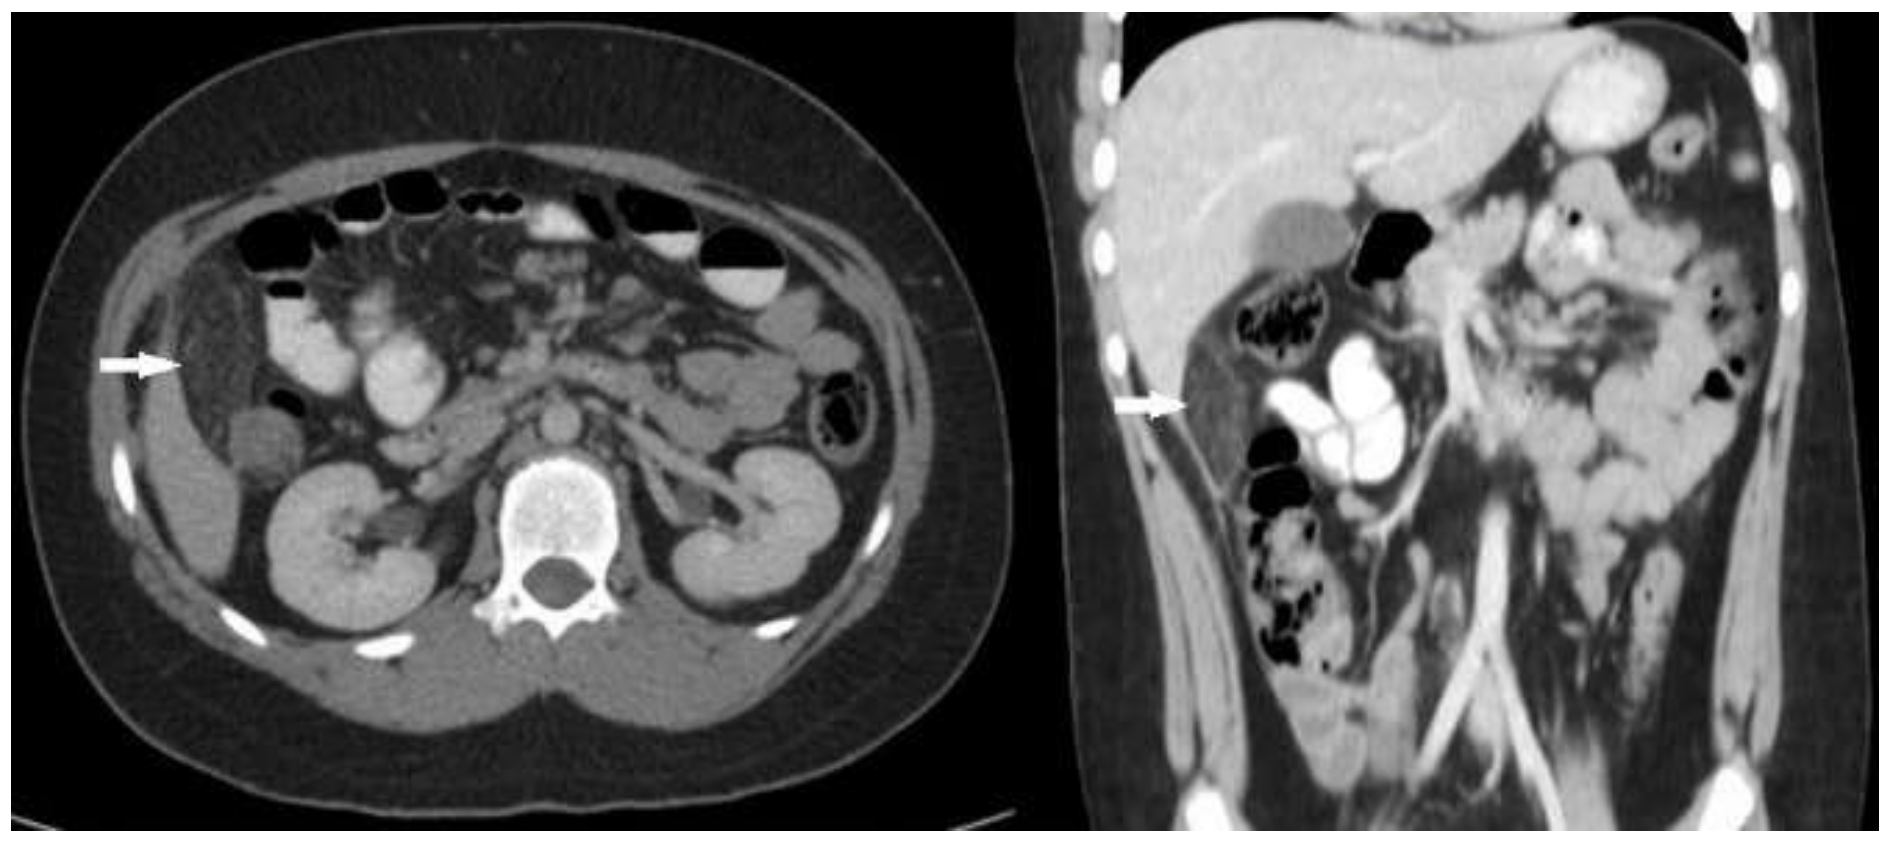

2. Case Report 1

3. Case Report 2